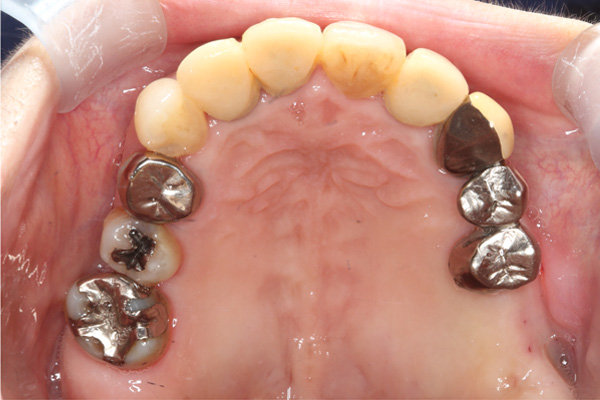

| 年代・性別 | 50代 男性 |

| 主訴 | 右上下の歯が痛い |

| 治療期間 | 約12ヶ月 |

| 費用 | 2,500,000円 |

| 治療内容 | インプラント、骨造成、結合組織移植、セラミック修復 |

| 治療に伴うリスク | インプラント周囲炎 セラミックの破折、脱離 |